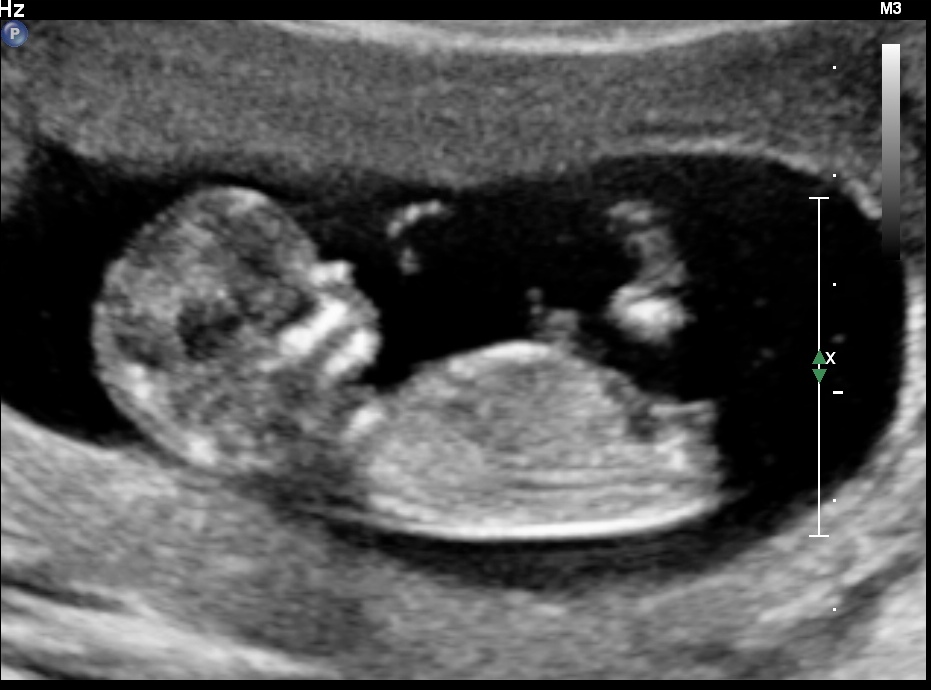

I'm new to this forum posting but I'm so curious if anyone has any guesses on what my lil bundle of joy is. So, what's everyone think- boy or girl? These were taken at my 12 week ultrasound.

What gestation based on O/LMP and what were you measuring as? I think it's probably a girl, especially if you're closer to 13w. If closer to 12w, I'm less confident.

Looks girly for now.....but it is still early and could change.....but I will say 70/30 girl :) congrats!

Tentative girl guess, but I agree it's early and you never know what a nub might do in just a week xx

I looks very much like a girlie nub :)

A slight girl lean. But still early.